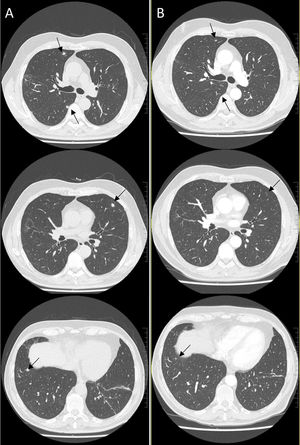

Varón de 67 años, exfumador desde hace 25 años (dosis acumulada: 20 paquetes/año), sin otros antecedentes relevantes. Ingresó por neumonía COVID-19 leve (oxigenoterapia de 2-3 l/min) y fue tratado con remdesivir y dexametasona 8mg/día durante 10 días, siguiendo por protocolo una pauta descendente de prednisona al alta. La tomografía computarizada de alta resolución de tórax de control a los 2 meses (fig. 1 A) mostró múltiples nódulos pulmonares bilaterales sólidos infracentimétricos junto a algunos tractos fibroatelectásicos.

El hallazgo de múltiples nódulos en la tomografía computarizada de alta resolución de pacientes con COVID-19 ha sido previamente descrito1. Sin embargo, la aparición de múltiples nódulos sólidos en fase tardía de neumonías COVID-19 leves sin otros hallazgos inflamatorios es atípica, haciendo plantear un diagnóstico diferencial con proceso neoproliferativo e infeccioso. No obstante, debido a la satisfactoria recuperación clínica del paciente sin signos de alarma, se decidió tratar con 5mg/día de prednisona y repetir una tomografía computarizada de alta resolución de tórax a los 3 meses (fig. 1 B), en la que se apreció una resolución progresiva de los nódulos. A pesar de no disponer de estudio anatomopatológico, dados la evolución radiológica y el contexto clínico, se orientaron como focos organizativos, que es una presentación radiológica infrecuente de neumonía organizativa2.